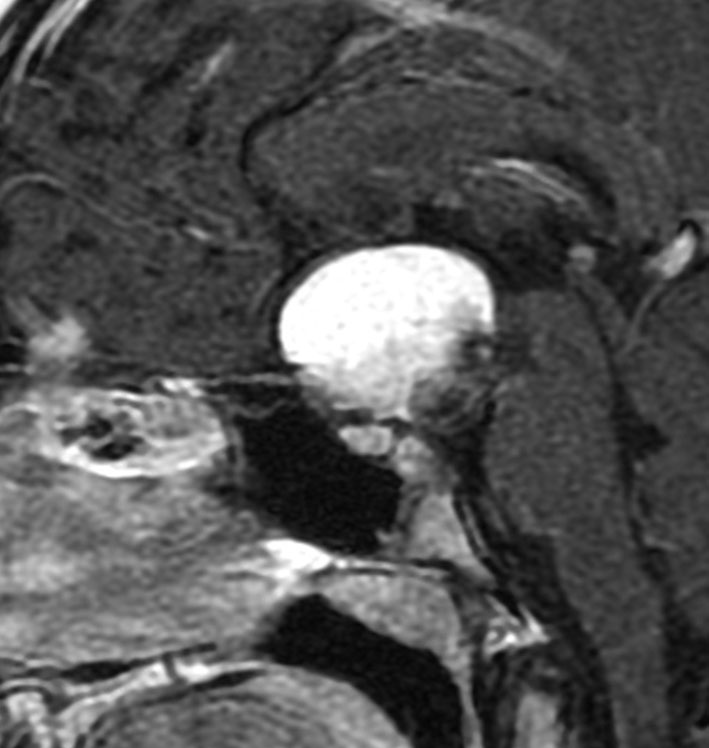

この子の症状は頭痛だけ。両親はなぜ気づかなかったのかと疑問を持ちますが,巨大になるまで症状が出ないこともあるのです。左のCTで腫瘍の周囲にバラバラと白い点状の石灰化があるので診断できます。左の視床下部から発生したクラニオでした。開頭手術しますが超高難易度です,怖いです (┯_┯) 複数回開頭手術になりましたが結果的に全摘出できています (by Dr 山本哲哉)。